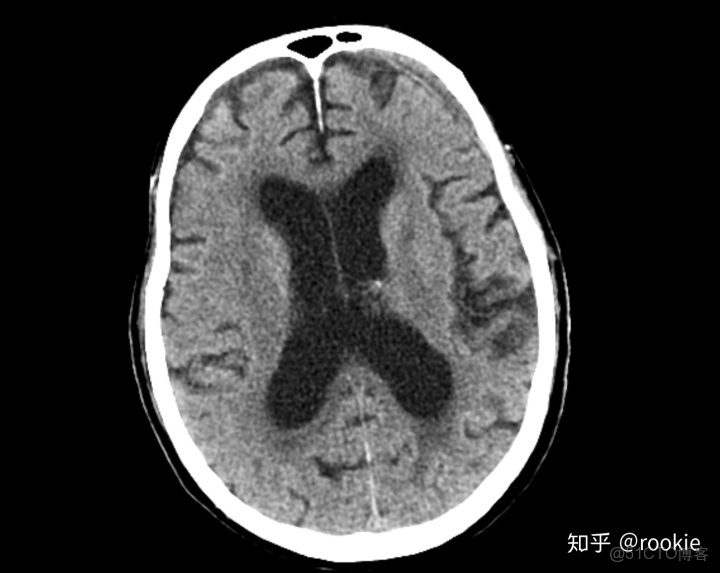

腦窗窗口設置: (W:70,L:30)或(W:70,L:35)優點: 此窗口旨在評估腦實質(通常在非對比掃描中),並且在拾取顱內出血時特別敏感,窗口狹窄且水平接近預期的腦出血密度。

CLAHE算法增強局部對比度的X光圖像增強效果對比_f5_15

腦窗是用來評估腦實質,經常被用來評估顱內出血,在這張圖片上有一個左額葉的慢性硬膜下血腫。